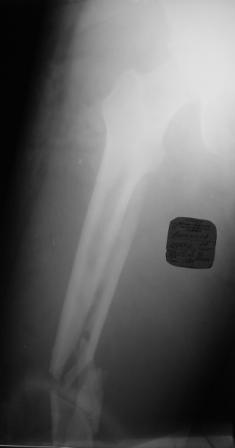

Хотелось узнать Ваше мнение по тактике лечения многооскольчатого перелома бедра

Пациент 26 лет, травма в результате ДТП. Находится на системе скелетного вытяжения.

Соматически уже компенсирован. Планируется выполнить остеосинтез бедренной LCP

пластиной на тракционном столе, при этом не хотим обнажать зону многооскольчатого

перелома. Буду благодарен за критические замечания по предложенной тактике и другие

светлые мысли!